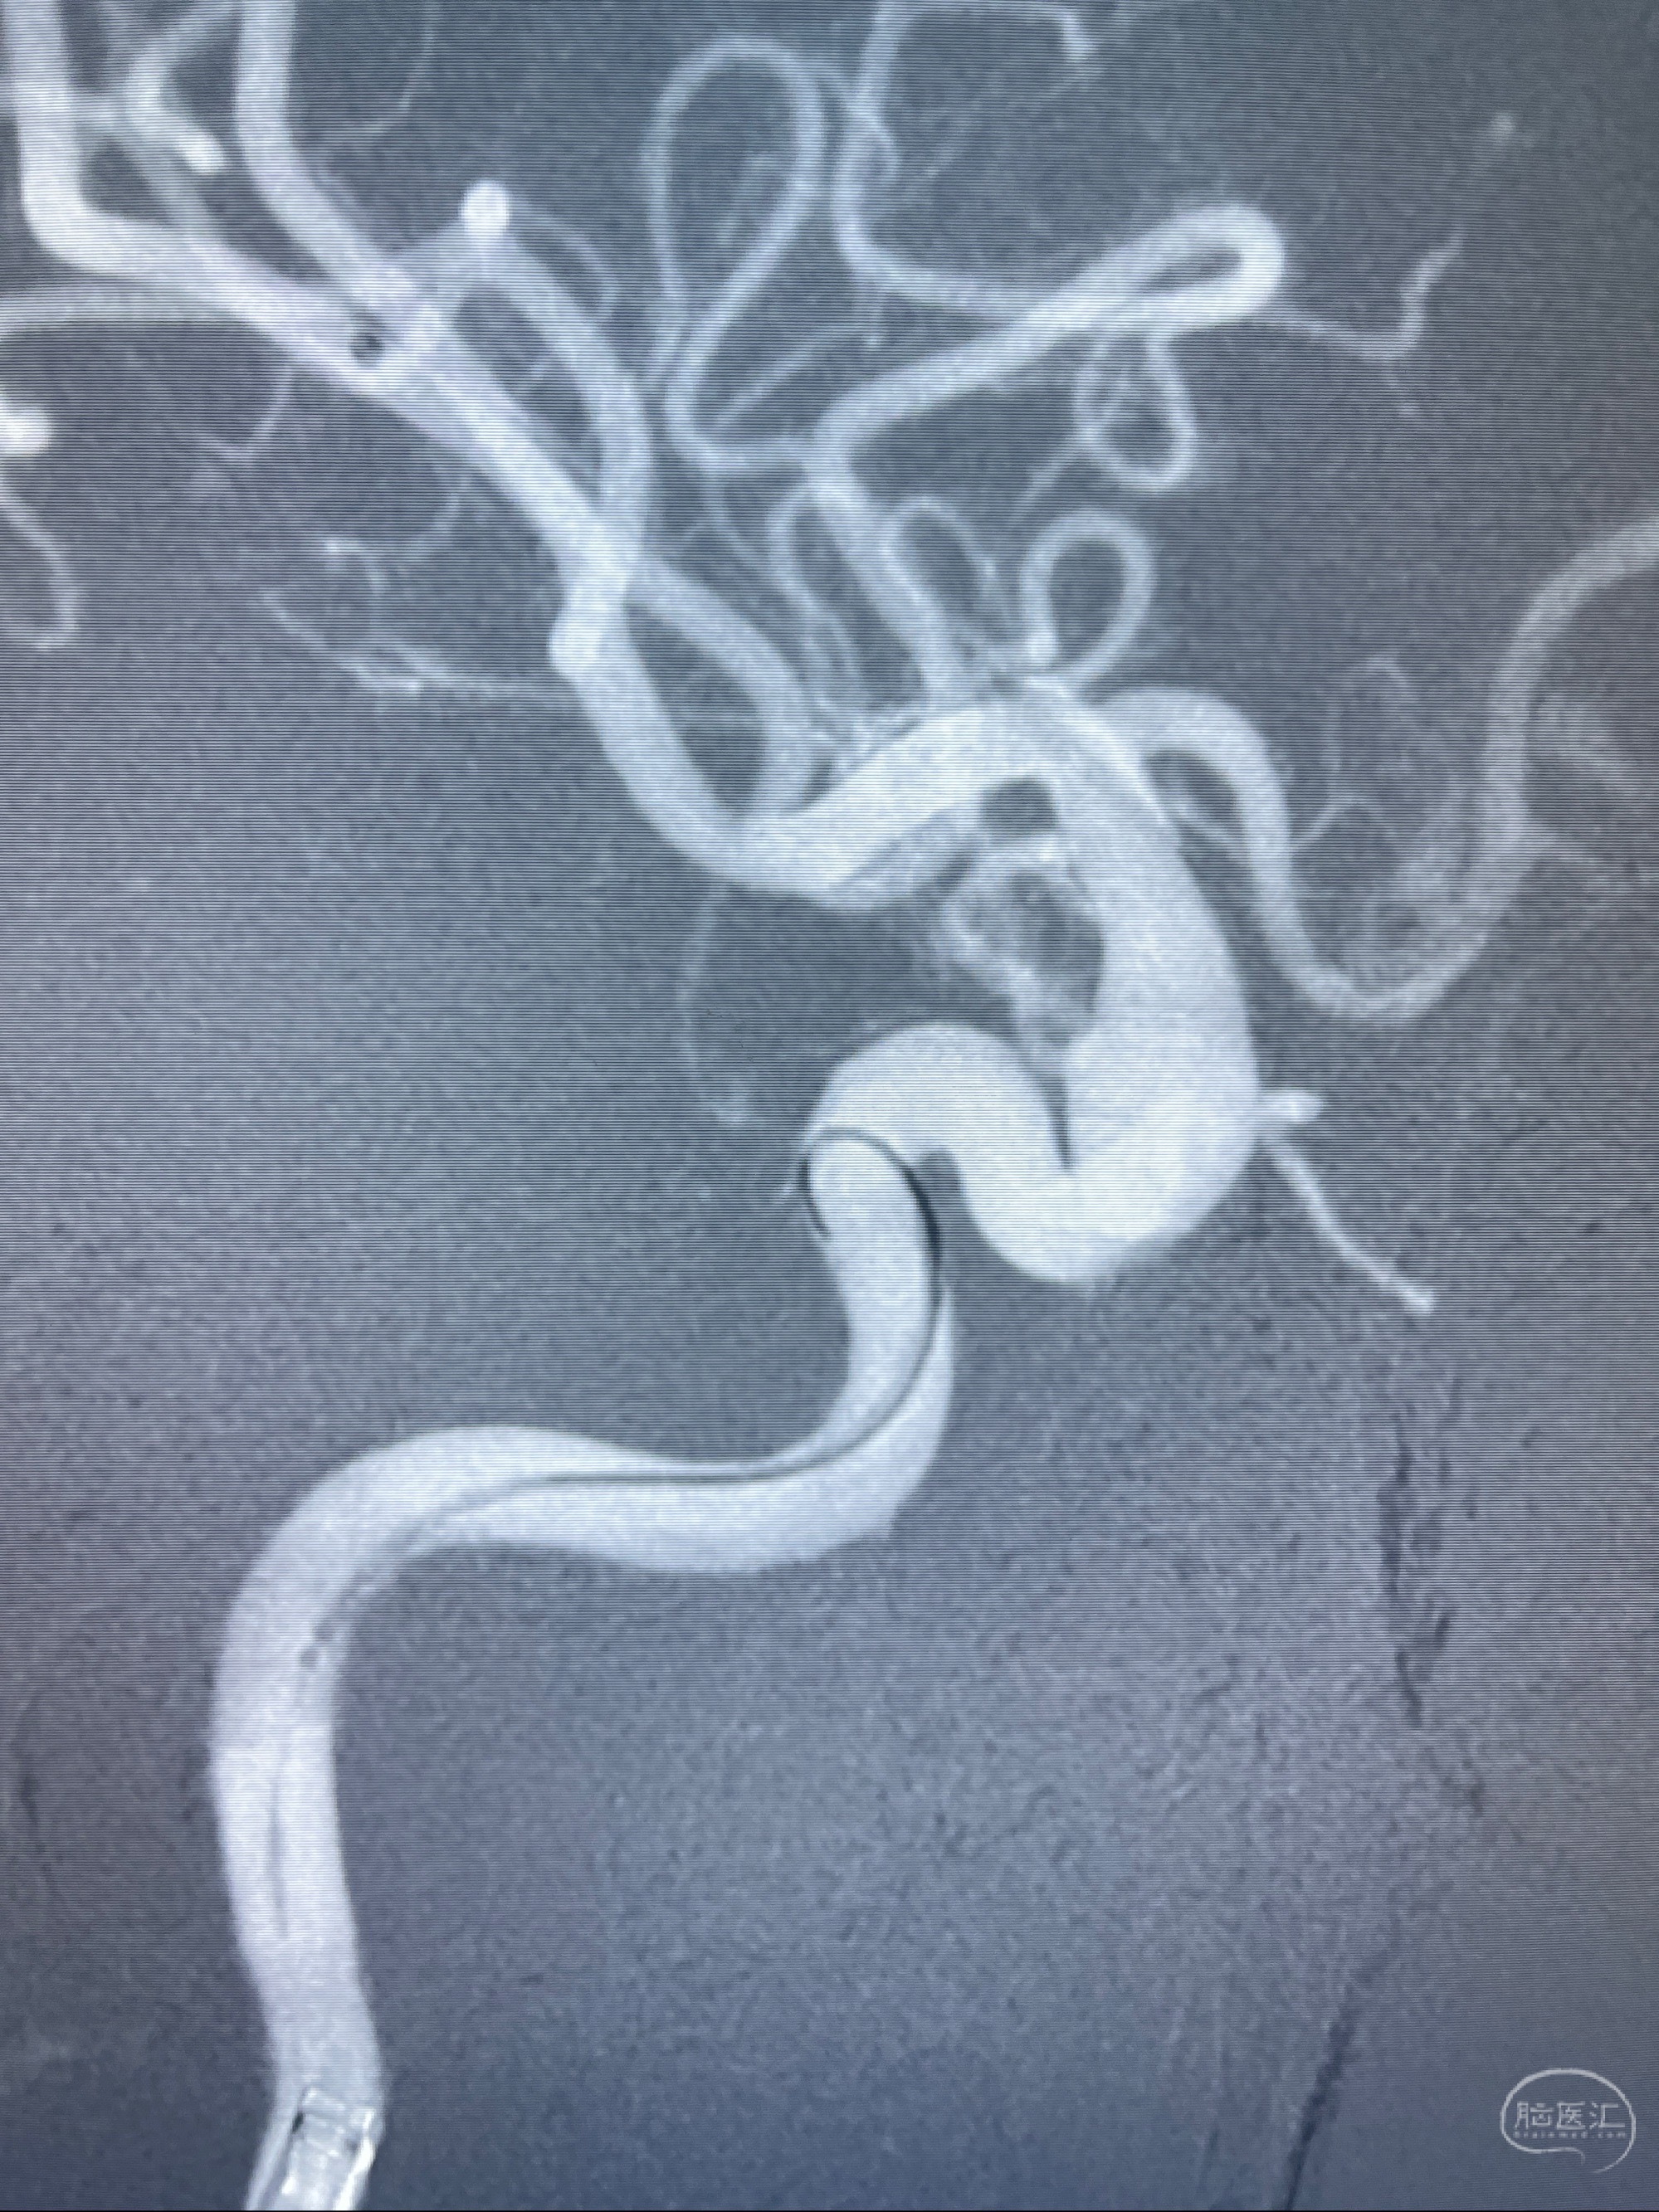

2023-07-27全脑血管造影:双侧颈内动脉眼动脉段动脉瘤,右侧较大

2023-08-01全麻下行双侧颈眼动脉瘤支架辅助栓塞

- pipeling4.5-20mm

- pipeline 4.0-20mm